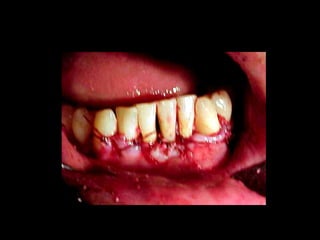

La periodontitis, denominada comúnmente piorrea, es una enfermedad que

inicialmente puede cursar con gingivitis, para luego proseguir con una pérdida de

inserción colágena, recesión gingival, e incluso la pérdida de hueso, en el caso de

no ser tratada, dejar sin soporte óseo al diente. La pérdida de dicho soporte

implica la pérdida irreparable del diente mismo.

De etiología bacteriana que afecta al periodonto (el tejido de sostén de los dientes,

constituido por la encía, el hueso alveolar, el cemento radicular y el ligamento

periodontal) se manifiesta más comúnmente en adultos mayores de 35 años, pero

puede iniciarse en edades más tempranas.

Periodontitis